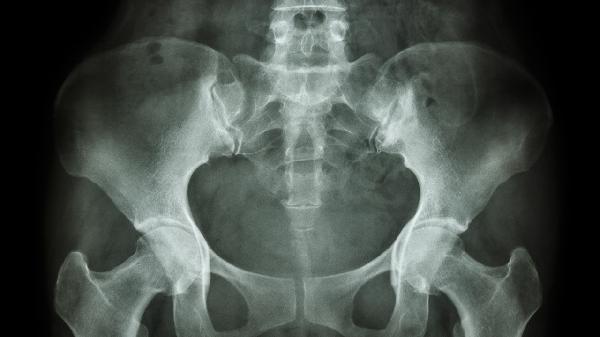

骨盆回旋可通过物理治疗、运动矫正、手法复位、佩戴支具、手术治疗等方式改善。骨盆回旋可能与不良姿势、肌肉失衡、外伤、先天发育异常、脊柱侧弯等因素有关,通常表现为腰骶部不适、步态异常、下肢不等长等症状。